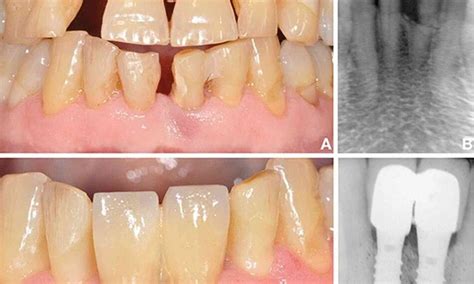

» Gallery 6-Immediate Dental Implant placement in a periodontaly ...

Gallery 6-Immediate Dental Implant placement in a periodontaly weakened ...

drmurugavel.in